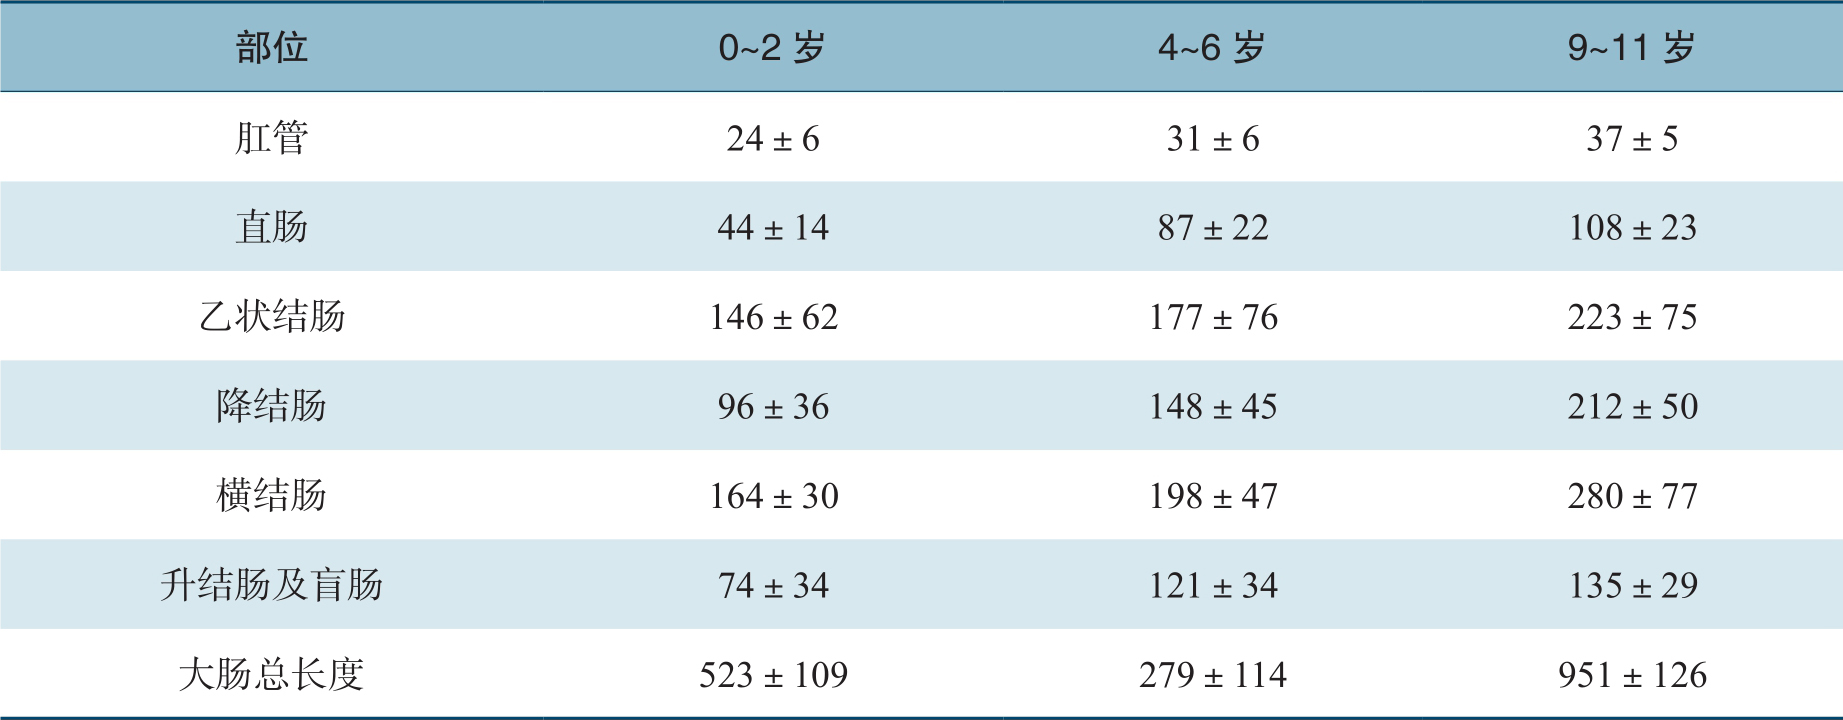

表2-1 结肠在不同年龄的长度

单位:mm